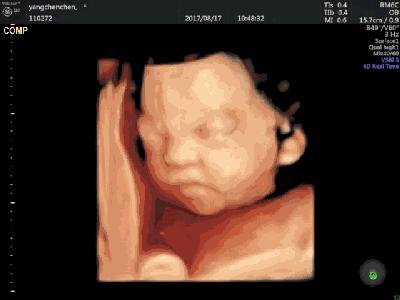

③ 宝宝的听觉:准妈妈在孕24周左右,宝宝就可以听到外界的声音了,并且声音越大,宝宝的反应也会越强烈哦~

④ 宝宝的视觉:在孕前27周时,宝宝的大眼睛一直都处在闭合的状态,但过了27周后,宝宝就能睁开眼睛,并眨眼哦,萌萌哒~